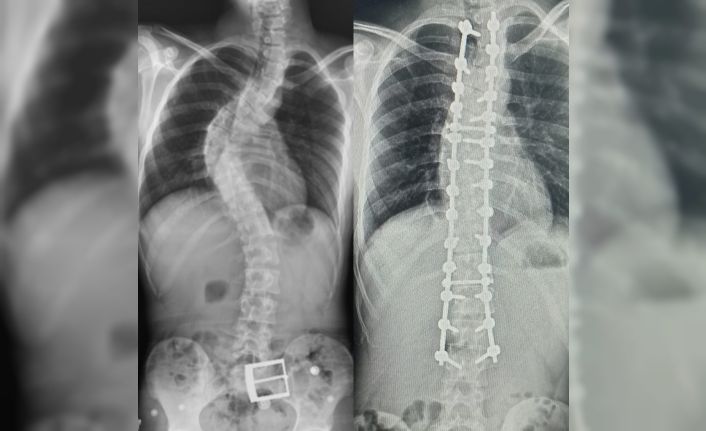

Yapılan muayene ve incelemeler sonucu hastada 73 derece skolyoz (omurga eğriliği) ve kifoz (kamburluk) tespit edilerek Ahmet Akan’a ameliyat önerildi. Samsun Üniversitesi Tıp Fakültesi Ortopedi ve Travmatoloji Anabilim Dalı Öğretim Üyelerinden Dr. Öğr. Üyesi Ömer Bozduman, deneyimli ameliyat ve anestezi ekibi eşliğinde görev yaptığı Samsun Eğitim ve Araştırma Hastanesi’nde 7 saat süren başarılı bir skolyoz ameliyatı gerçekleştirdi.

Hasta ile ilgili bilgi veren Dr. Öğretim Üyesi Ömer Bozduman, “Hastamız artan sırt ağrıları ve omurga eğriliğinin ilerlemesi şikâyetiyle kliniğimize başvurdu. İnceleme ve değerlendirmelerimiz sonucu ameliyat kararı verdik. 7 saat süren skolyoz ameliyatını takiben 12 saat sonra hastamız kaldırılıp yürütüldü. Ameliyat sonrası nörolojik olarak hiçbir sorunu yok. Eğriliği tamamen düzeldi, boyu uzadı. Şu an kendisi yürüyüp gezebiliyor. Hastayı 5 gün sonra taburcu edip evine gönderiyoruz. Her ameliyatta olduğu gibi skolyoz ameliyatlarında da ekip çalışması çok önemlidir. Uzun süren bu ameliyatı, hastanemizin özverili ameliyat ve servis hemşireleri ve deneyimli anestezi ekibi ile gerçekleştirdik” dedi.